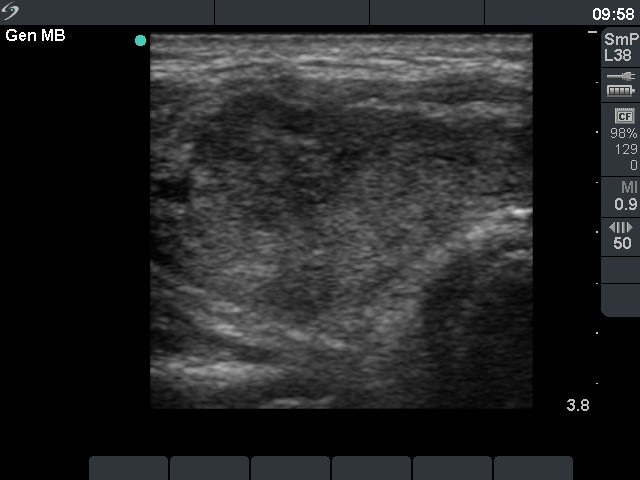

Ultrasonography : the thyroids were echonormal. There was a cystic nodule with an echonormal solid part in the right lobe.

Five sessions of sclerotherapy were performed. We gave 19.8 mL alcohol during five sessions of ethanol sclerotherapy. We demonstrate the first and the third sessions.